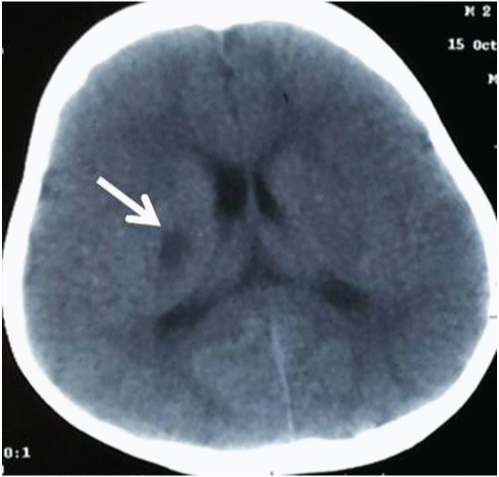

A two-year-old male child presented with acute onset of weakness of left upper and lower limb. There was no facial deviation. He underwent unenhanced computed tomography (CT) scan of the brain in a different hospital and was diagnosed with acute in-farct in the right capsulo-ganglionic region [Table/Fig-1]. Further routine blood investigations and biochaemical investigations did not reveal any abnormality. There was slow improvement in power of the limbs. He was referred to our institute for further evaluation with magnetic resonance (MR) imaging 2 months after the initial onset of symptoms. MRI of the brain along with three- dimensional time of flight (3D- TOF) MR angiography of cervical and intracranial vessels was performed. MR imaging of the brain revealed a chronic infarct in the right capsulo-ganglionic region [Table/Fig-2].

NECT SCAN – Fairly defined hypodense area in Right Capsulo-ganglionic region (White arrow)